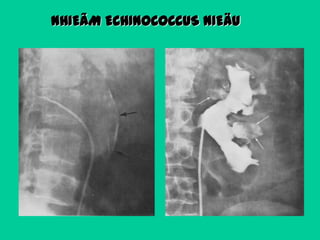

NHIEÃM KYÙ SINH TRUØNG

Coù theå laø caùc ñoùng voâi ôû thaønh

nang saùn vôùi daïng voøng hay daïng

quaû leâ.

Nang KST coù theå kheùp kín, nhöng ña

soá môû vaøo moät ñaøi thaän neân

thaáy

ñöôïc

bôø

ngoaøi

khi

chuïp

ñöôøng nieäu vôùi thuoác caûn quang.

Caùc

nang

lôùn

“daughter cyst”.

coù

theå

chöùa

NHIEÃM ECHINOCOCCUS NIEÄU